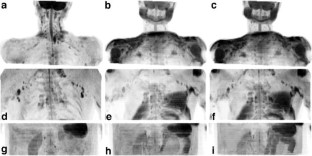

The purpose was to provide a diffusion-weighted whole-body magnetic resonance (MR) imaging sequence with background body signal suppression (DWIBS) at 3.0 Tesla. A diffusion-weighted spin-echo echo-planar imaging sequence was combined with the following methods of fat suppression: short TI inversion recovery (STIR), spectral attenuated inversion recovery (SPAIR), and spectral presaturation by inversion recovery (SPIR). Optimized sequences were implemented on a 3.0- and a 1.5-Tesla system and evaluated in three healthy volunteers and six patients with various lesions in the neck, chest, and abdomen on the basis of reconstructed maximum intensity projection images. In one patient with metastases of malignant melanoma, DWIBS was compared with 18F-fluorodeoxyglucose positron emission tomography (FDG-PET). Good fat suppression for all regions and diagnostic image quality in all cases could be obtained at 3.0 Tesla with the STIR method. In comparison with 1.5 Tesla, DWIBS images at 3.0 Tesla were judged to provide a better lesion-to-bone tissue contrast. However, larger susceptibility-induced image distortions and signal intensity losses, stronger blurring artifacts, and more pronounced motion artifacts degraded the image quality at 3.0 Tesla. A good correlation was found between the metastases as depicted by DWIBS and those as visualized by FDG-PET. DWIBS is feasible at 3.0 Tesla with diagnostic image quality.

Fig. 1